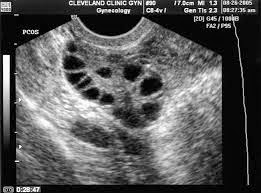

Gambar Usg Sel Telur Matang

BEGINI GAMBAR SEL TELUR YANG SUBUR… - dr Yudhistya SpOG | Facebook Story of My Journey: TTC Journey #2 USG Folikel dan Hasil Analisa Sperma Aku dan PCOS (Hasil USG Trans Vaginal) - JalanSenja.com Cerita Promil 4 - Polycystic ovary (PCO) - Fika Putri Cerita Promil 2 - USG Transvaginal dan Tes Sperma - Fika Putri Semua Akan Terjawab di Waktu yang Tepat - kumparan.com Promil Story : MIMPI BURUK ITU BERNAMA PCOs - The Arsalan Family Journal Penting Dilakukan Wanita, Ketahui Sel Telur Dalam Tubuhmu Jangan Sampai “Mandul” Karena Kehabisan Program Hamil di Dokter Lusiana Irene, SpOG Jogja Manusia sedikit tahu..sel telur kecil tidak mungkin hamil | Dr Suryo, SpOG - Kesehatan Reproduksi C e r i t a C i k i: Sel Telur Kecil-Kecil EFEK PENYUBUR Pada wanita normalnya sel… - dr Yudhistya SpOG | Facebook Ikhtiar yang ke dua – Part 2 (H6-H11) – Bread and Butter Letter Promil Step 4 – Baby Journey PCOS adalah… | Kisah Ibuknda (pakai ‘k’) :D Room | ‘Aisyah Tsurayya Inart’s Story - Yah, Saya Akhirnya Hamil - I’m 1 In 10: My PCOS Story Kisah Perjuangan Terbaru Tya Ariestya Saat Jalani Program IVF | Popmama.com story of my lyfe: pejuang keturunan Nikita Mirzani Bagikan Hasil USG Bayi Kembar, Dapatkah Gen Kembar Diturunkan? - Semua Halaman - Intisari lihat hasil USG tranvaginalku wktu bulan Januari 2013 apa itu PCO? - IbuHamil.com Cerita Promil 4 - Polycystic ovary (PCO) - Fika Putri aq PCO bund, ada yg bisa bantu baca hasil USG intravagina q??? - IbuHamil.com Hasil USG Sel Telur Yang Subur - YouTube Pengalaman Bayi Tabung/ IVF (Part II) Update with Pict! | honeymenulis’s Blog Inart’s Story - Yah, Saya Akhirnya Hamil - Story of My Journey: June 2017 Ingin Terhindar dari Kista? Jauhi 4 Jenis Makanan Enak Ini Sekarang! - Semua Halaman - Grid Health Program Hamil Bulan ke-1 : PCOS Survivor | Lanalouie Embrio 3 cm berapa minggu. minggu: bayi Anda sebesar tongkol jagung BEGINI GAMBAR RAHIM YANG SUBUR… - dr Yudhistya SpOG | Facebook PCOS | medicalstudentnotes USG Transvaginal: Penjelasan, Prosedur & Manfaat (Lengkap) | Friso BILIK SONOGRAFER : Kista Ovarium Kontrol H+10 (Cek Perkembangan Sel Telur) Istilah kehamilan dipertimbangkan dengan USG. Kehamilan kebidanan dan embrio Selamat Pagi Senin Ayah Bunda. Semoga… - Dokterkandungan. id | Facebook My First USG | Story of Us Menuju Hamil – Part 2 of 3 – Edward Suhadi Apa itu PCOS? Kenapa Sulit Hamil? | Sunshine of My Life Setiap Ibu Hamil Harus Tahu, Kapan Harus Melakukan USG lewat Vagina? - Semua Halaman - Nakita Program Hamil di Dokter Lusiana Irene, SpOG Jogja Saat Sel Telur Berukuran Kecil dan Sulit Dibuahi - Health Liputan6.com Kabar Gembira, Ini Tanda Awal Sel Telur Berhasil Dibuahi oleh Sperma | Popmama.com 101+ Gambar Cek Sel Telur Paling Hist - Gambar Pixabay Kontrol H+12 (Mendebarkan, apakah sel telurnya tetap berkembang?) Program Kehamilan Balasan dari Saya Penderita PCOS, Saya Berhasil Hamil | KASKUS Pembekuan Sel Telur: Fungsi, Prosedur, dan Komplikasi INGIN HAMIL – Siklus Ovarium dan Tanda-Gejala Wanita Subur | JuliantoWitjaksono.com 6 Fakta Mengejutkan Tentang Sel Telur Wanita - YouTube Pengalaman Hamil Kembar - The Urban Mama Maimuns — PCOS? Deal with it! Berapa Sisa Sel Telur di Tubuh? Bisa Dicari Tahu | Parenting.Dream.co.id PCOS Polycystic Ovary Syndrom Apakah… - Komunitas Impian Bunda | Facebook Persiapan Hamil (4) – jurnal Ammi Wanita Hasilkan 2 Sel Telur dalam Masa Ovulasi, Bisakah Terjadi? Promil Story : MIMPI BURUK ITU BERNAMA PCOs - The Arsalan Family Journal My journey to motherhood: HSG, Tes Sperma, hingga PCO Polikistik Ovarium (PCOS): Haid sering tidak datang, Berkumis, Berjerawat, Ingin hamil sulit | Dr Suryo, SpOG - Kesehatan Reproduksi PCOS dan Metformin. Sohib karib! – Cerita Bumi Blighted Ovum | ~cahaya kebaikan~ Cerita Pengalaman Kehamilan Pertama dan Persiapan Melahirkan Anak Pertama - For The Love of Foods and Beauty Masih banyak yg belum tau.. INSEMINASI… - Bayi Tabung PMC Pekanbaru Cerita Program Hamil dengan Dokter Enny Sp.OG di Yogyakarta ~ Land of Jenganten Semua Akan Terjawab di Waktu yang Tepat - kumparan.com Fika Putri Berbagi Tips: Cara Mengetahui Masa Subur Wanita Berdasar Penghitungan serta Ciri-Cirinya - Garda Remaja GAGAL OVULASI?? SERING TERJADI PADA… - Konsultasi Promil Cepat Hamil dan Alami | Facebook Yosevina Issabela prosespersalinan Instagram posts (photos and videos) - Picuki.com Apa sebetulnya bayi tabung dan bagaimana proses menjalaninya? – Bayi Tabung Penang Di minggu kebidanan mana embrio terlihat. Minggu berapa embrio terlihat pada USG? Apakah prosedurnya aman pada tahap pembentukan anak PCOS itu Variable dan Sangat Rumit Prosedur Bayi Tabung: Sebelum dan Sesudah Mengikutinya - Smarter Health Mengenal Kehamilan Kosong atau Blighted Ovum (BO) - Kompasiana.com Cerita Promil, Perjalanan menuju kehamilan (long story short, I finally got pregnant) - Nyonyah Intan Sindrom Ovarium Polikistik (PCOS) 4D Gallery | Dr Suryo, SpOG - Kesehatan Reproduksi Kapan USG direncanakan selama kehamilan. Apakah saya perlu mempersiapkan prosedur? Keadaan organ reproduksi wanita Irish Bella Hamil Anak Kembar, Sang Ibunda Tak Sangka Bakal Punya 2 Cucu - Halaman all - Tribun Batam Lapsus Kista Ovarii - Apriamalia - [PDF Document] Success story – GLADIOOL IVF RS Indosehat Solo, Jl Solo Sragen Km 11, Kebakramat, Karangdawa (2020) Saya Penderita PCOS, Saya Berhasil Hamil | KASKUS September 2014 - Pipit Widya Aku dan PCOS (Hasil USG Trans Vaginal) - JalanSenja.com Pengalaman PCOS-ku yang Berhasil Hamil Alami - kumparan.com Apakah USG mempengaruhi kehamilan. Bagaimana ultrasound mempengaruhi embrio? Ultrasonografi dilakukan hanya atas kesaksian dokter atau mungkin atas permintaan ibu BAB III - [DOCX Document] Kista Ovarium. - ppt download Biaya USG 3 & 4 Dimensi di Karawang - Perawatan Kesehatan Cerita Pengalaman Kehamilan Pertama dan Persiapan Melahirkan Anak Pertama - For The Love of Foods and Beauty Wanita Punya 400 Sel Telur Setiap Menstruasi, Kenapa Susah Hamil? - Semua Halaman - Nakita Tragis Si Ibu Hamil Dibunuh, Bayi di Dalam Kandungan Dicuri - Halaman all - Warta Kota Perlukah USG Transvaginal saat Program Hamil? | Popmama.com 13 Tanda - tanda Kehamilan Awal yang Bisa Dipercayai - Mamapapa.id Melahirkan bayi kembar pada minggu-minggu kehamilan. Dapatkah dokter tidak melihat bayi kembar dengan USG: diagnosis dini kehamilan ganda PROSES DAN BIAYA INSEMINASI 1. USG USG… - dr Yudhistya SpOG | Facebook